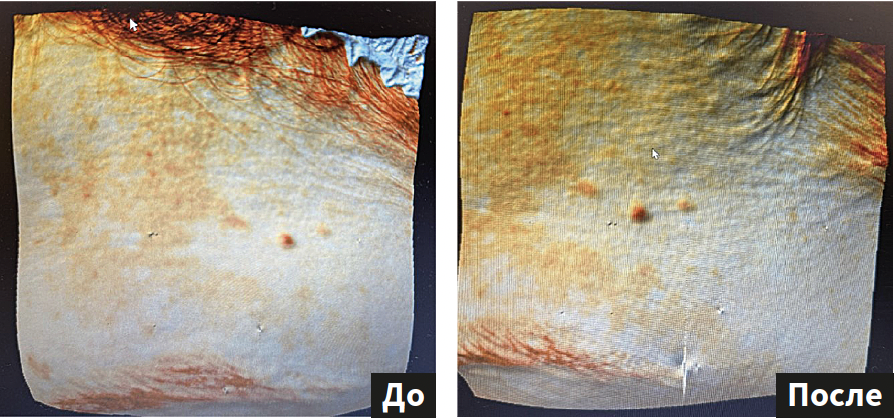

Результат. Домашний уход от бренда BIOTIME на основе антиоксидантов и различных форм топических ретиноидов в течение 28 дней показал высокие результаты против гиперпигментации смешанного эпидермально-дермального залегания (рис. 1–3).

Рис. 1. Оценка количества пигмента на аппарате Antera 3D |

Рис. 2. Визуализация пигмента под ультрафиолетовым освещением |